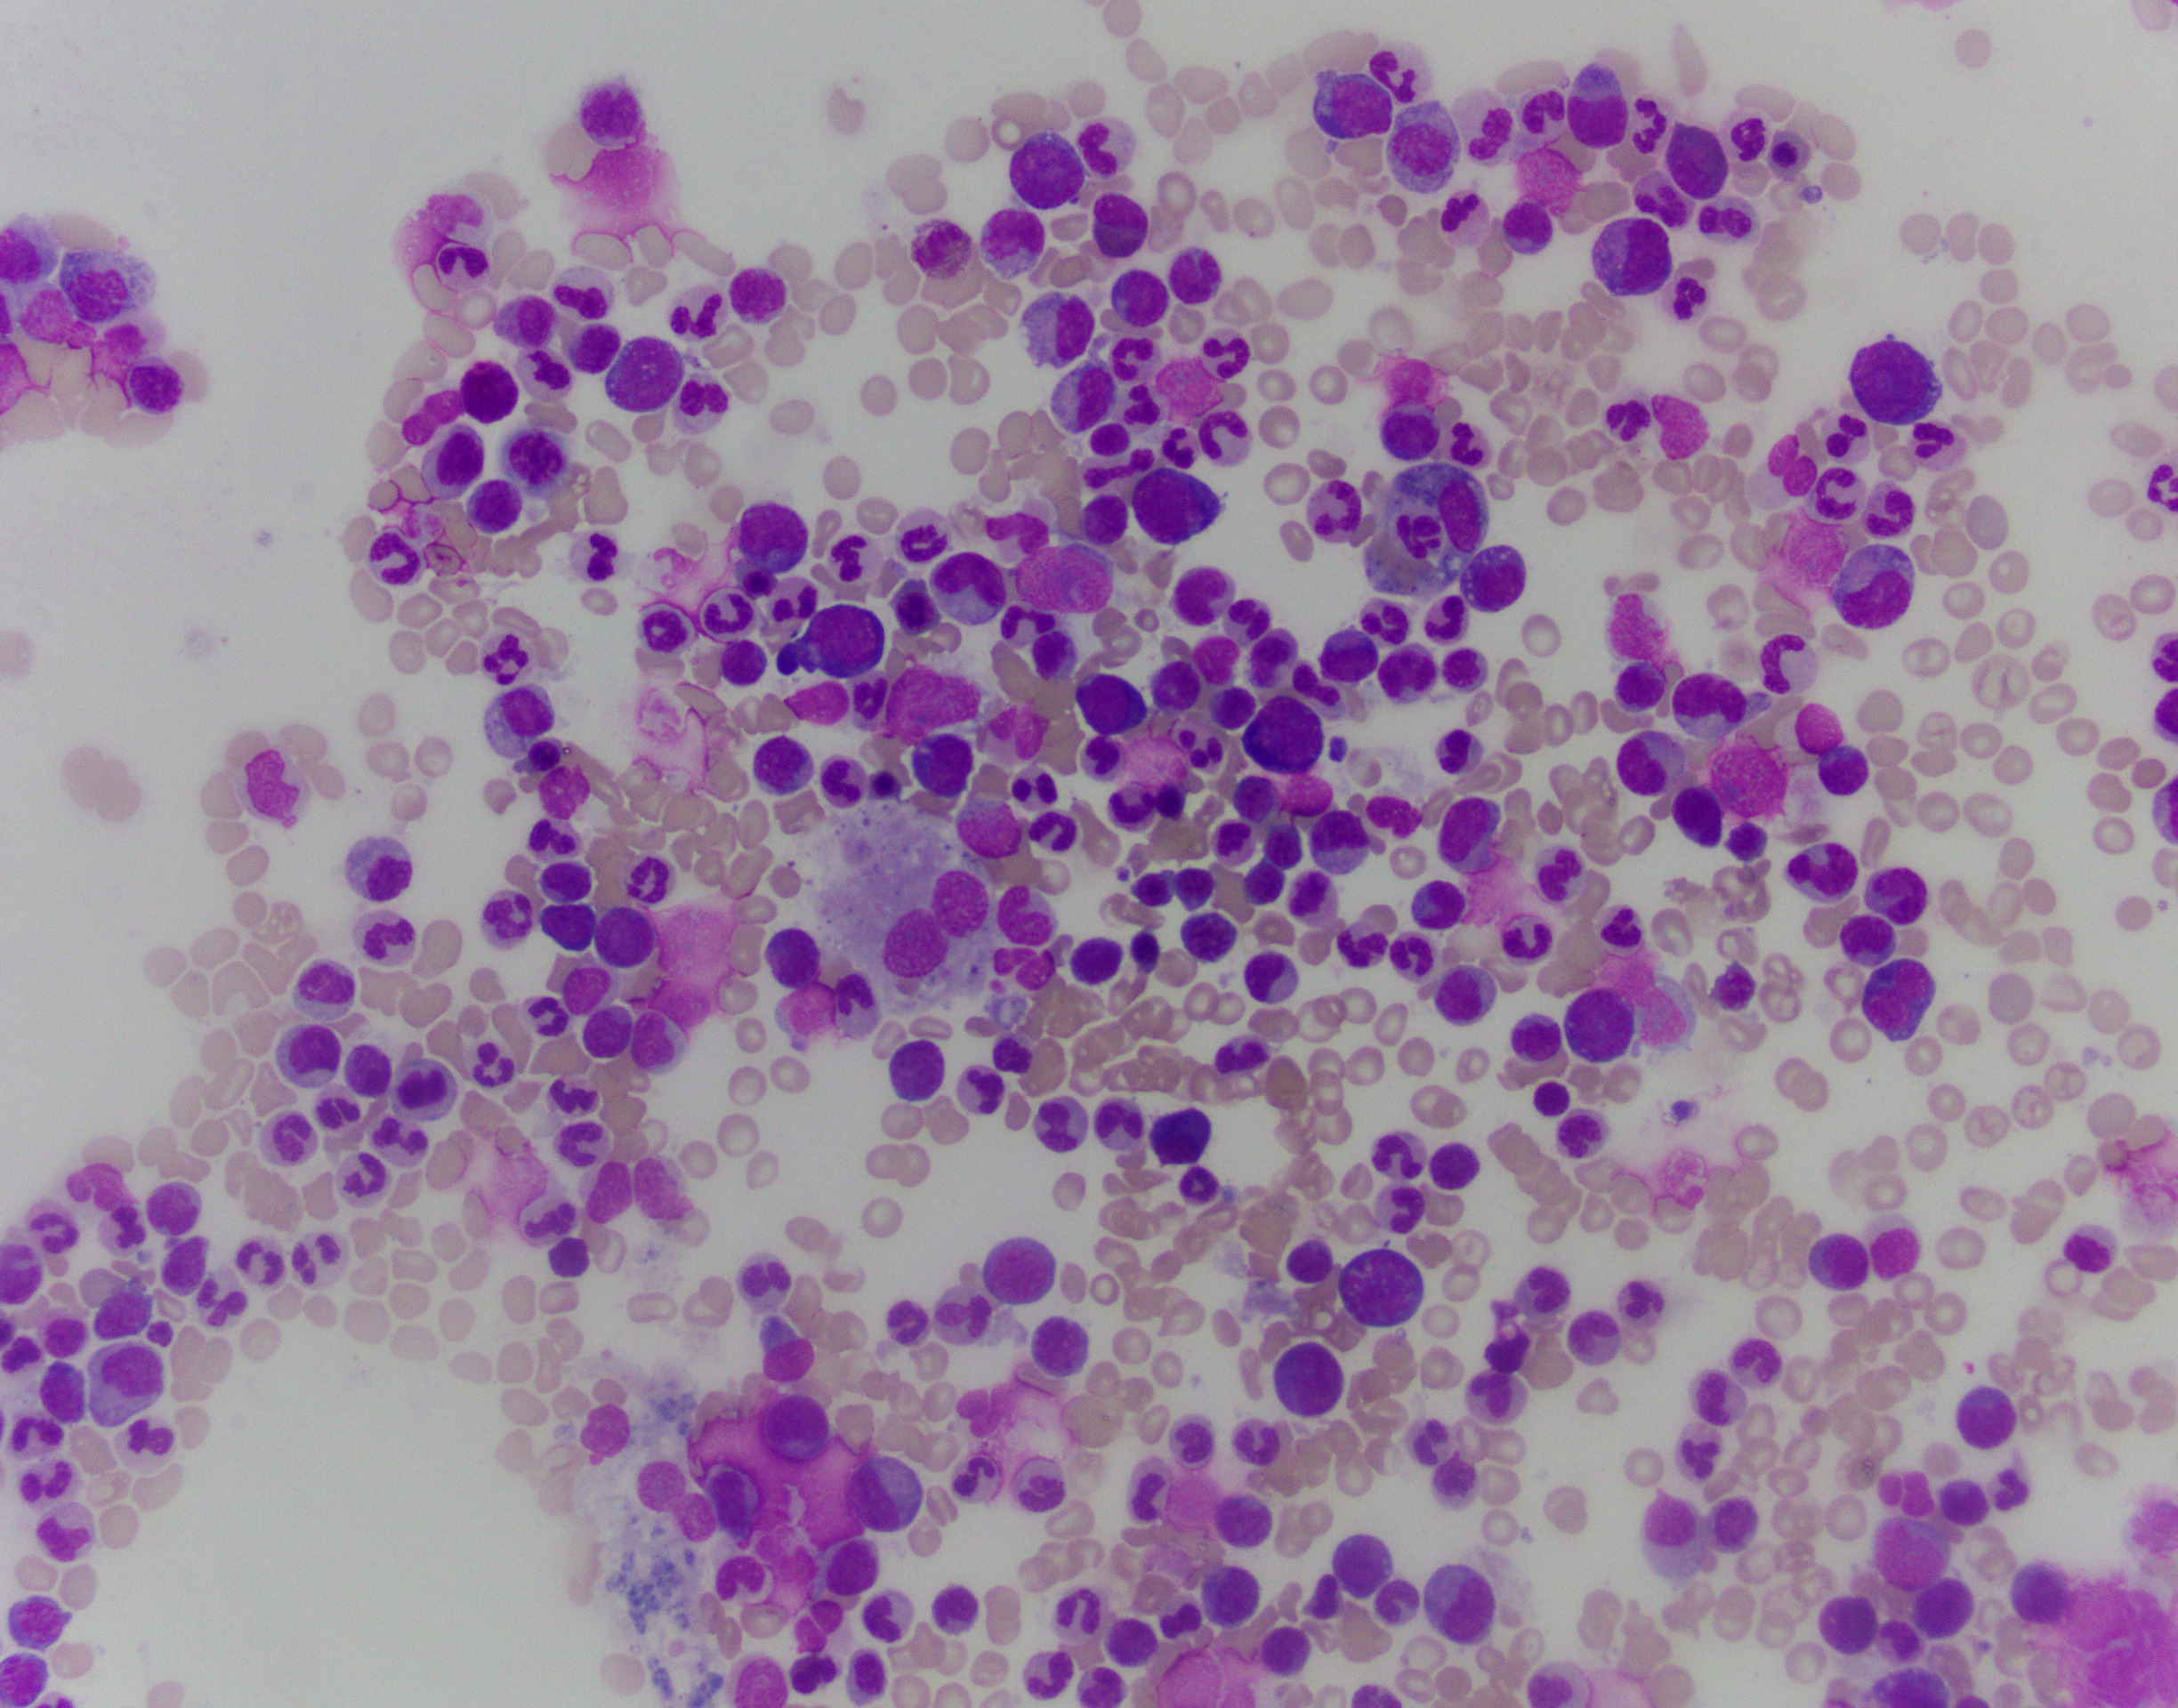

The patient is a 76-year-old male with anemia (Hgb 8.6) and thrombocytopenia (15,000/microliter). Of note, serum copper levels are low. Photomicrographs of the bone marrow aspirate and biopsy are provided.

The patient's bone marrow biopsy shows a hypercellular marrow with dysmegakaryopoiesis and no overt increase in blasts on routine stains. In a patient with cytopenias and this morphology, the diagnosis is unfortunately rarely straightforward. The differential diagnosis of entities that can cause morphologic dysplasia is long and includes infection, medications, autoimmune processes, nutritional deficiencies, and myeloid neoplasms. Follow-up of concurrent cytogenetic and molecular tests is essential for further classification; however, a normal karyotype does not fully rule out a myelodysplastic syndrome.

Copper deficiency is notorious for being a mimicker of MDS, and supplementing copper and observing the patient's CBC and possibly repeating a biopsy may be necessary in this patient. While definitely a possibility, this case is not classic for pure copper deficiency. Thrombocytopenia is less common, and the classic morphologic findings in copper deficiency are dysplasia in the erythroid lineage with cytoplasmic vacuoles in the erythroid and granulocytic lineages.